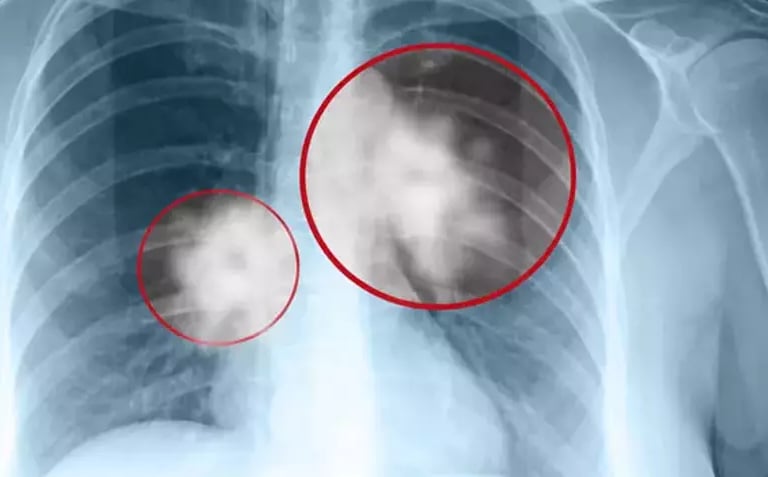

4. Tanısal Kartografi: Görüntüleme ve Moleküler Profilleme

Düşük Doz BT (LDCT): Tarama için altın standarttır. Nodül çapı 8 mm üzerine çıktığında ve kenar yapısı "spiküle" (dikenli) olduğunda, malinite riski Bayesyen eğride dikey bir tırmanışa geçer.

Radyolojik Görüntüleme Analizi

Görüntüleme BulgusuLR+LR-Analitik FarklılaşmaAkciğer Grafisi (Mass/Kitle)15.0 - 20.00.70Grafi negatifi kanseri dışlamaz (LR- 0.7 yüksek).Periferik Nodül (Düzensiz/Spiküle)10.0 - 12.00.15Adenokarsinom lehinedir; spikülasyon malignite olasılığını katlar.Hiler/Mediastinal Genişleme8.0 - 10.00.25Santral yerleşimli tümörler (Squamous/Small Cell) için kritiktir.Thorax CT (Kontrastlı)3.50.09Tanısal Altın Standart: Negatif bir CT, kanser olasılığını %90'dan fazla düşürür.MRI (Pancoast Değerlendirme)~30.0 (Staging)0.10Brachial pleksus ve vasküler invazyonu CT'den daha iyi gösterir.